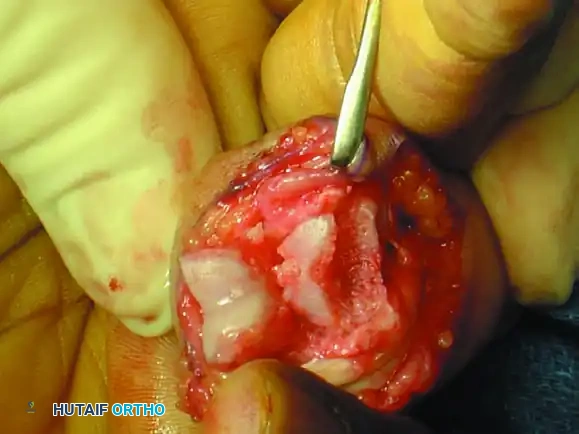

Figure 67-49A: Persistent dorsal PIP joint subluxation with a nonreconstructible middle phalangeal volar lip fracture.

Figure 67-49B: Volar exposure of the middle phalangeal base and geometrical preparation of the defect to receive the graft.

- Volar Approach: A volar Bruner or midlateral incision is made to approach the PIP joint. The flexor tendon sheath is opened, and the A3 pulley is released. The flexor tendons are retracted laterally.

- Joint Exposure ("Shotgunning"): The volar plate is released distally. The collateral ligaments are sharply released from their proximal attachments to allow the joint to be hyperextended or "shotgunned." This provides unparalleled visualization of the articular defect on the middle phalanx.